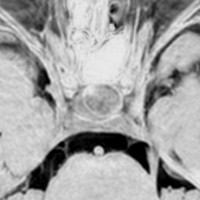

9歳の女の子に偶然発見された腫瘍です。何の症状もありませんでした。頭蓋咽頭腫と診断されて経過観察となりました。1年半観察しましたが腫瘍は増大して,視交差の変形が増して両耳側1/4半盲となり症候性となりました。下垂体機能は正常でした。

上のT2強調画像では,全体的に低信号で,高信号の部分が混在します。上右のCISS画像では,下垂体組織が右に変移していることが推定されます。

左がT1強調画像で高信号,右がT1ガドリニウム増強像ですが腫瘍は増強されません。正常か錐体が腫瘍の右側にくっついていて,ガドリニウム増強されています。典型的なトルコ鞍部黄色肉芽腫です。画像診断で,下垂体腺腫の腫瘍内出血とよく間違われるのですが,高信号になるのはコレステリン結晶を豊富に含むからです。ガドリニウム増強される部分がほとんどないという所見が頭蓋咽頭腫とは異なるところでしょう。

左と中央の画像でinfundibular recessの管腔が見え,左の視交差から視索の変形が強いことが解ります。右の画像では下垂体組織がトルコ鞍の右側に偏在してあります。画像では正常化錐体と明瞭な境界があるように見えるのですが,実際の手術所見では正常下垂体との境界は不鮮明でした。腫瘍のう胞からは黒褐色の内容液 machinery oil とコレステリン結晶が流出しました。厚いのう胞壁は硬膜と下垂体に強く付着して剥離するのが困難で切断して摘出しました。ラトケのう胞とはのう胞壁の厚さが異なると言えます。